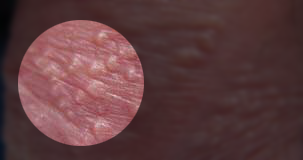

2、尖锐湿疣:病初为淡红或污红色粟状大小的红痘痘,形态如丘疹状、乳头状、菜花状、鸡冠状,性质细嫩、顶端稍尖,无痛痒感,渐渐长大或增多。红痘痘基底稍宽或有带,表面有颗粒,表面湿润或有出血,在颗粒间常集中有脓液,散发腐臭气味,搔抓后可继发化脓。